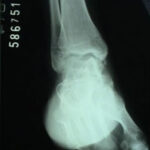

Artroscopia para Artrose do Tornozelo

Durante a artroscopia para artrose, verificamos e tratamos várias lesões. Realizamos sinovectomia, desbridamento e retirada de corpos livres, conforme citado anteriormente. A abrasão do osso subcondral exposto e o restabelecimento dos canais de vascularização e formação de fibrocartilagem podem trazer benefícios. O desbridamento artroscópico na artrose de tornozelo é um procedimento paliativo, que visa alívio temporário da dor em pacientes que ainda apresentam alguma amplitude de movimento. Sendo assim, se houver indicação para artrodese via artroscópica, removemos toda a superfície articular do pilão tibial, domo talar e superfícies talomaleolares medial e lateral (cruentizadas) com shaver e curetas até a exposição de osso esponjoso viável. Tomamos os devidos cuidados para evitar retirada excessiva de cartilagem e osso subcondral, que podem criar deformidades em varo ou valgo. Deformidades angulares prévias podem ser corrigidas artroscopicamente ou via aberta.

Ressecamos o osteófito anterior para possibilitar a redução do domo talar na articulação do tornozelo. Após preparar a área a ser artrodesada, inserimos dois guias canulados para o drill, um lateralmente através do maléolo lateral e um medialmente, através do maléolo medial. Porém, a angulação dos guias canulados será de 30° inferior e 30° anterior, partindo dos maléolos. Utilizamos fluoroscopia para verificar a posição correta da artrodese. No plano sagital, desejamos a posição neutra de dorsiflexão e flexão plantar do tornozelo e no plano coronal o calcâneo deve estar em 5° de valgo. Finalmente, utilizando parafusos canulados de 6,5mm através do guia, concluímos a artrodese.